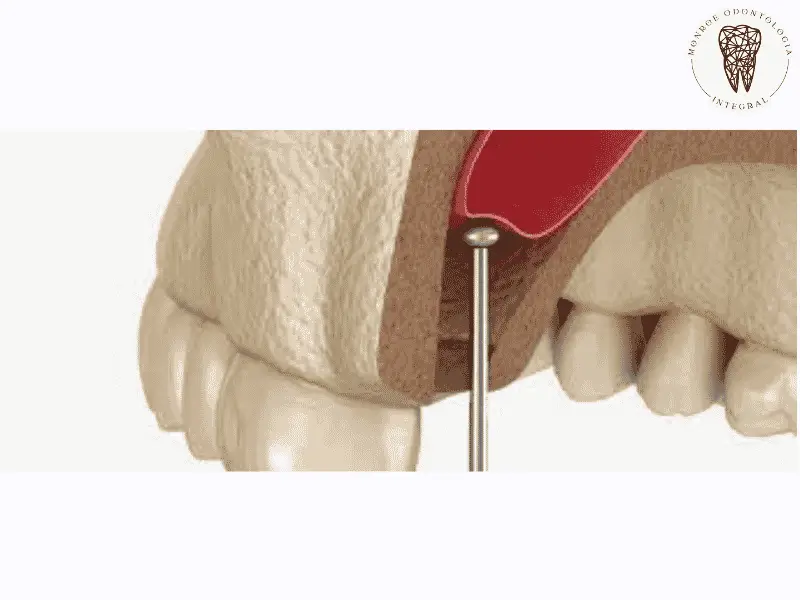

La gingivectomía con láser es un tratamiento innovador y efectivo para corregir sonrisas gingivales, mejorando tanto la estética como la salud dental. Este procedimiento no solo elimina el exceso de tejido gingival, sino que también garantiza una experiencia sin dolor para los pacientes. Con técnicas avanzadas y un enfoque en la comodidad del paciente, la gingivectomía con láser se ha convertido en la opción preferida para quienes buscan una sonrisa perfecta. Descubre cómo este tratamiento puede transformar tu salud dental y tu confianza personal.

Gingivectomía con láser: una solución moderna y efectiva Leer más